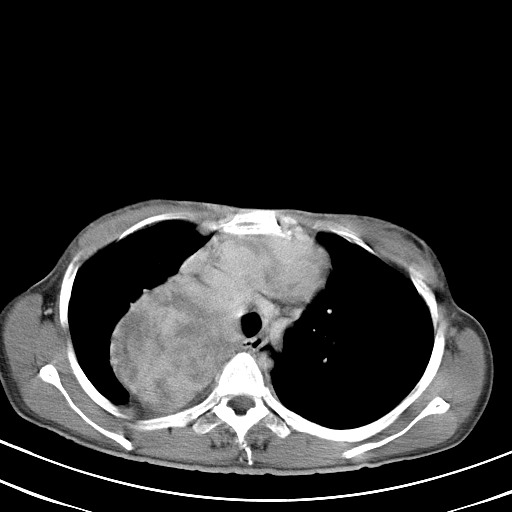

以下是引用汪涛同志在2007-8-2 0:40:00的发言:[br]病变虽然广泛,同时侵及双侧纵隔,但是无论左侧和右侧上下观察都是与右侧颈部甲状腺相延续的,而且强化幅度基本一致,又同时具有恶性病变病变的某些特征:肿块过大且密度不均,部分层面与正常纵隔结构分界不清,结合病史已有两年,考虑:胸内甲状腺肿恶变可能。[br]